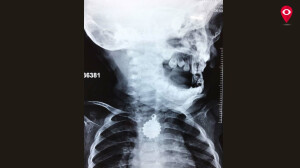

Doctors said that the locket was stuck in the food pipe, which was causing the problem. Dr. Shashikant Mashal performed the endoscopy and removed the locket without any cut.

“Rukaiyya’s family was petrified owing to the girl’s condition. When we did a check-up we found out that the locket was stuck in her food pipe. Our challenge was to remove the locket safely as it had sharp edges. Thankfully, the procedure went successfully. Now, Rukaiyya is stable and doing good,” said Dr. Shashikant Mashal, ENT specialist, Cooper Hospital.